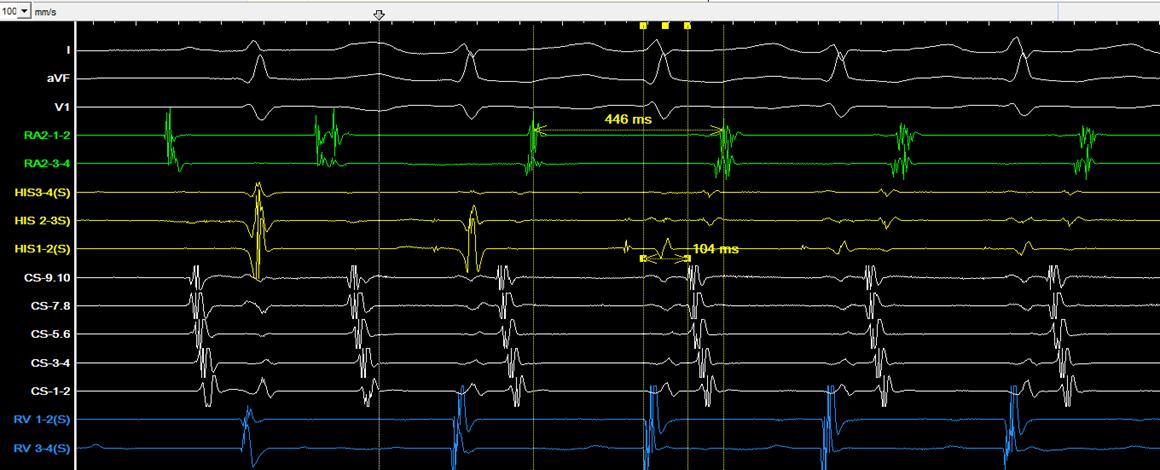

急診室, 3 歲時發作的 12 導程心電圖為 short RP narrow QRS tachycardia ( 圖一、發作時 ) ,因 RP interval 為 120 ms,orthodromic AVRT的可能性較大,retrograde P wave 的型態為I: +/-, II/III/aVF: -, V1: +,delta RP interval of III and V1: 0 ms ,根據 Tai et al. 的研究可以推論可能是 concealed posterior septal accessory pathway(1)。使用 adenosine後,tachycardia可以被矯正回sinus rhythm (圖 二、沒發作時 ) 。自出生後就一直服用 betablocker ,但 仍時常發作,因此在 13 歲時,我們安排了心導管電生 理檢查, RV burst pacing 時最早的 retrograde atrial activation是CS ostium,PAC時會誘發tachycardia (TCL: 446 ms) with the same retrograde atrial activation (concentric) when RV burst pacing (圖三),Ventricular overdrive pacing during tachycardia呈現VAV response with SA-VA of 48 ms and PPI-TCL of 72 ms (圖四),在 VOP 時 fusion beat can reset the next A ( 圖五 ) , Hisrefractory VPC can reset the next A (圖六),在tachycardia 時有出現RBBB pattern也沒有延長TCL (圖七),Antegrade conduction 經由 fast AVN ,綜合以上判斷 orthodromic

AVRT with concealed left posterior septal AP,於是在RV pacing時,我們先從RPS region開始mapping沒有發現有 VA fusion site,然後我們就到retrograde transaortic到LPS region mapping也沒有找到VA fusion的位置,接著我們 的電燒導管在 CS 裡 mapping 時突然掉進 MCV ,這裡發

(圖六)、His-refractory VPC reset the next A

(圖七)、RBBB during tachycardia did not prolong TCL

(圖八)、VA fusion when tachycardia in MCV